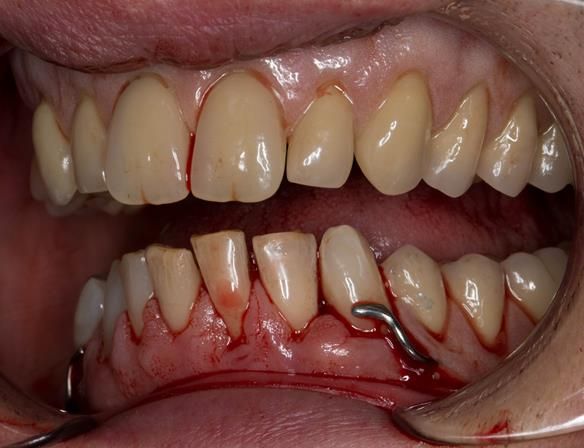

This 52 year old man was referred to me from his general dental practitioner in 2018.

10 years prior to consultation the patient's general dentist diagnosed periodontitis and referred him to Manchester Dental Hospital. He received a treatment plan to manage the periodontitis. Unfortunately, this was not acted on. Four years ago gaps developed between the upper front teeth. Orthodontic treatment was provided to align the teeth. A bonded retainer was fitted onto the upper front teeth. Approximately one year prior to consultation with me the patient noticed the teeth moving again. He consulted his orthodontist, who advised no further orthodontic treatment. One month prior to the consultation with me the upper left central incisor fell out whilst eating.

- Generalised periodontitis; stage IV grade C: currently unstable, risk factors: smoker.

- The remaining maxillary teeth had hopeless prognosis in the short term. They exhibited 80 - 100% alveolar bone loss with increased mobility (Grade 2 - 3).

- The lower right second premolar and lower left first premolar (LR5 LL4) had hopeless prognosis in the short term. They exhibited 80 - 100% alveolar bone loss with grade 3 mobility.

- The remaining mandibular teeth had approximately 30 - 50% alveolar bone loss with grade 1 mobility.

The clinical situation and treatment process is shown in detail below with photographs.